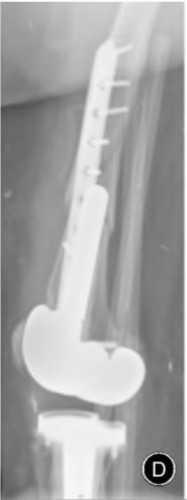

A 67-year-old man who underwent total hip arthroplasty (THA) 4 years ago fell on to his right hip. His pre-injury right hip film is seen in Figure A while films of his current injury are seen in Figures B and C. Prior to the fall he had no thigh or hip pain. His ESR and CRP are within normal limits. During intraoperative assessment, the acetabular and femoral stems are found to be well fixed. What is the next best course of action?

This patient has a periprosthetic hip fracture at the level of the stem with a stable prosthesis, indicated open reduction and internal fixation as the treatment of choice.

The Vancouver Classification can be helpful in clinical decision-making regarding fixation versus revision of periprosthetic hip fractures of the proximal femur. A stable implant, by nature, does not need to be revised in the setting of adequate bone stock for fixation, but the ultimate test of stability should be in the operating room. Many fixation strategies are appropriate, but many implants include locking plate fixation for concerns of stress-shielded bone around the implant as well as use of unicortical fixation at the level of the stem.

Pike et al review the current trends in treating B1 fractures including locking plates with strut allografts, minimally invasive plate osteosynthesis (MIPO) and locking plates spanning femoral THA and TKA stems in selected patients. The authors conclude that no studies currently provide evidence establishing one

technique over the other and recommend treatment on a case by case basis.

Illustration A shows a possible fixation construct for this patient's fracture. The Vancouver Classification is seen in Illustration B and Illustration C represents an algorithm for treatment options.